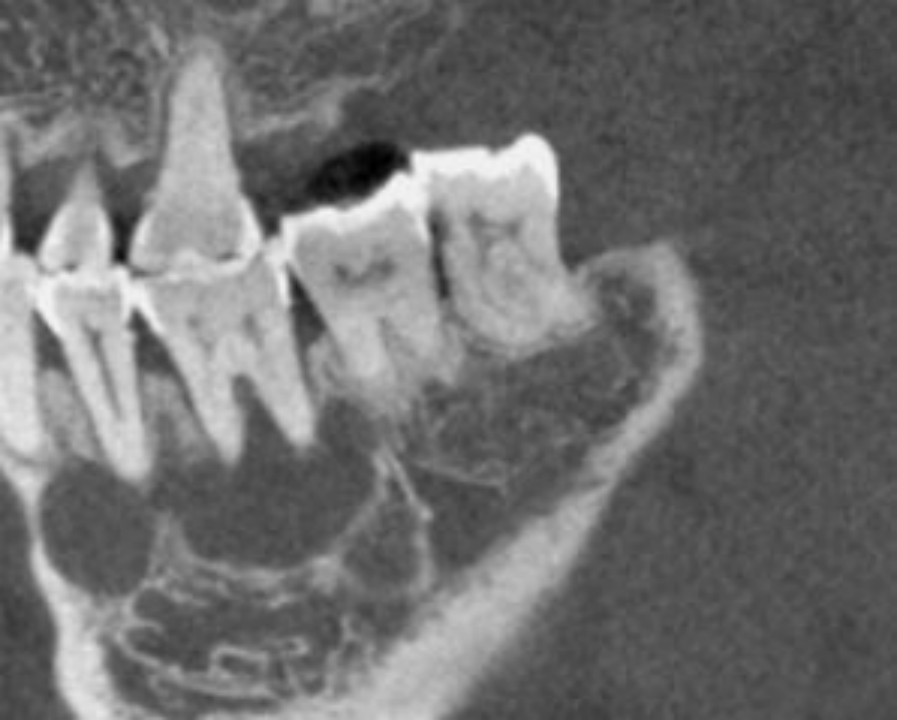

如果脓液长期压迫颌骨,形成了囊肿,不及时治疗的话,囊肿会越长越大,侵蚀骨头形很大的空腔,最后这个牙也只能拔掉。

这颗牙的根尖出现了很大的阴影,表明存在大面积的病变,但是她的牙齿里面根管的通路被堵上了,所以治疗很困难。

医生通过显微根管治疗成功打通根管,又通过手术把根尖区的囊肿摘除掉,慢慢恢复。通过根管治疗和根尖外科手术,既实现了保留牙齿的目的,又清除了病变。